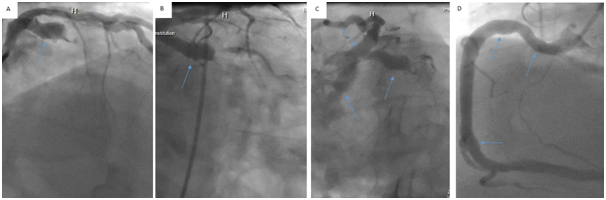

Cardiac catherization showed:1) diffuse coronary artery ectasia (CAE) with a chronic occlusion at the mid- left circumflex (LCX), 2) large caliber left main (LM) with mild luminal abnormalities, 3) large caliber left anterior descending (LAD) with diffuse aneurysms proximally and a large aneurysmal diagonal branch, 4) an aneurysmal right coronary artery (RCA) with an occlusion at the mid segment near the bifurcation of the small marginal branch and 5) a severely diffuse aneurysmal right common femoral artery with moderately diffuse plaques. (Figure 1)

Figure 1 Blue arrows indicate aneurysms. (A) Left coronary artery (LCA) cranial right anterior oblique view. (B) LCA right anterior oblique view. (C) LCA Spider-View and (D) RCA left anterior oblique view.